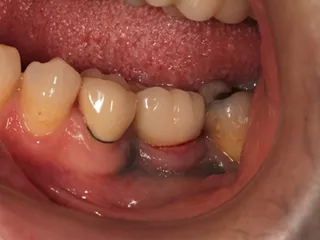

CASE No.1 奈良 嘉峰 先生(神奈川県茅ヶ崎市開業)

Labrida 施 術 前

施 術 前 (レントゲン写真)

Labrida 施 術 後(4週後 )

炎症とBOP消失

施 術 後 (レントゲン写真)